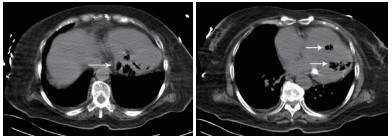

患者女性,75岁。因“被发现晕倒在地伴大小便失禁6 h余”于2018年10月25日12:10入院。患者为独居老人,当晚失联,入院6 h前,家人在家中发现其神志不清,大小便失禁,卧于床边,后患者家属呼120送至本院急诊科。入院后详细追问病史,患者身边无药瓶,家中亦无煤烟味。既往有“冠心病陈旧性心肌梗死、高血压病、2型糖尿病”病史11年余,“卵巢癌术后放化疗”病史2年余,“直肠占位”病史半年余。入院急诊体格检查:体温36.0℃,脉搏80次/min,呼吸17次/min,血压108/52 mmHg(1 mmHg=0.133 kPa),老年女性,神志不清,烦躁,面色苍白,皮肤湿冷、散在花斑,皮肤黏膜无破损。双侧瞳孔等大等圆,对光反射存在,言语、伸舌及肌力检查不合作,双肺呼吸音清,未闻及干湿性啰音,心率80次/min,律齐,心脏各瓣膜听诊区未闻及杂音,肝脾肋下未及,双下肢无水肿,四肢可见不自主活动,双侧病理征未引出。入院后心电图提示肢体导联及胸导联均有T波低平或倒置,V4-V6导联ST段压低(图 1)。血常规:白细胞计数32.35×109/L,中性粒细胞比率84.7%,中性粒细胞计数27.4×109/L,血红蛋白64 g/L,血小板计数221×109/L;CRP 111.9 mg/L,PCT > 100 ng/mL;肌酸激酶1 847 U/L,肌酸激酶同工酶356 U/L,肌酐219 μmol/L,肌钙蛋白T 6 257 pg/mL,NT-proBNP > 35 000 pg/mL。入院后急查颅脑、胸部及全腹CT,胸部CT提示左心室、室间隔及肺动脉根部区域见不规则条状、条片状低密度影,参考CT值约-200~-900 HU(气体密度影),外周伴伪影,左心室为著,外周分布为主,似累及心肌区域,部分心肌变薄,心包区域尚连续,主动脉系统未见气体影(图 2~3)。12:45患者病情急剧进展,呼吸心搏骤停,予气管插管、心肺复苏及药物抢救治疗,13:25抢救无效临床死亡,患者家属拒绝尸检。

| 示左心室、室间隔见不规则条状、条片状低密度影,参考CT值约-200~-900 HU,提示为气体影,左心室为著,外周分布为主,似累及心肌区域,部分心肌变薄,心包区域尚连续(白色箭头所示) 图 2 患者胸部CT结果 |

| 示气体影以左心室为著,外周分布为主,似累及心肌区域,部分心肌变薄(黑色箭头所示) 图 3 患者胸部CT冠状位影像 |

本例患者恶性肿瘤、糖尿病病史等使患者免疫功能低下,易合并重症急性感染。胸部CT显示左心室、室间隔及肺动脉根部区域见不规则条状、条片状低密度影,测量CT值提示为气体密度影。2016年Laiq等[1]曾报道因感染性心内膜炎致患者左心室内气体形成一例,患者血培养提示柠檬酸杆菌生长,最终患者发生急性心力衰竭,紧急二尖瓣置换术,术后乳头组织同样培养出柠檬酸杆菌,经抗感染治疗预后良好。2014年Alladina等[2]也曾报道一例因播散性肺克雷伯杆菌感染、产气,气体进入血液系统引起的脑空气栓塞。另外,临床工作中某些有创诊疗中,如深静脉置管、肺穿刺活检等也可能引起心脏空气栓塞[3-4]。但本例报道患者脑动脉、主动脉等大动脉系统未见明显气体影,说明患者左心室内气体不具有流动性。仔细观察胸部CT影像学表现,气体在左心室内主要沿室壁分布,部分心肌壁变薄,综合考虑为左室心内膜炎可能。左室内气体位于心内膜下,不在心腔内,故不具备游走性,这也就能解释为何患者其他动脉系统血管内不存在气体的原因。